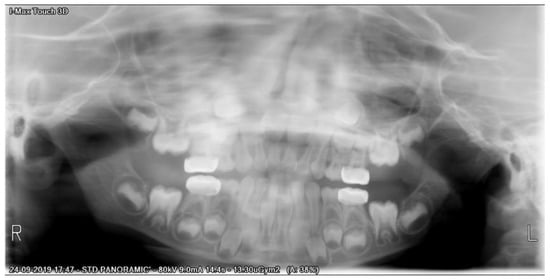

After a three-month period, we performed a panoramic radiograph (Figure 4), and every six months, clinical and radiograph exams were collected. At the end of four years of follow-up, clinical evaluation revealed a good marginal adaptation and gingival health (Figure 5), and radiographic exam showed normal occlusion in all the first permanent molars (Figure 6). Moreover, at each appointment, information was given regarding gingival health, occlusal contacts, adaptation of crown margins, and the presence of clinical signs of infection. No additional treatment was needed during the follow-up period.

Figure 6. Panoramic X-ray of four-year follow-up.